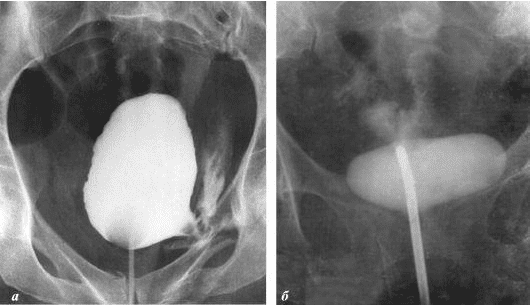

Želim da vam pokažem neke fotografije tako da sami možete da vidite šta se dešava urogenitalnom sistemu i drugim organima muškarca koji nema seksualne odnose.

Evo kako izgleda upala prostate uzrokovana stagnacijom sperme (kada se testisi ne prazne). Trajna upala dovodi do adenoma prostate, a kasnije do raka prostate (prema statistikama, 38% muškaraca umire zbog ovoga). Zbog odsustva seksa, ovo se dešava uvek i to je razlog zašto se adenom prostate naziva "bolešću starih".

Rak prostate kod muškarca starog 58 godina. Uzrok - dugotrajna apstinencija (od 51 godine). Pacijent je umro.